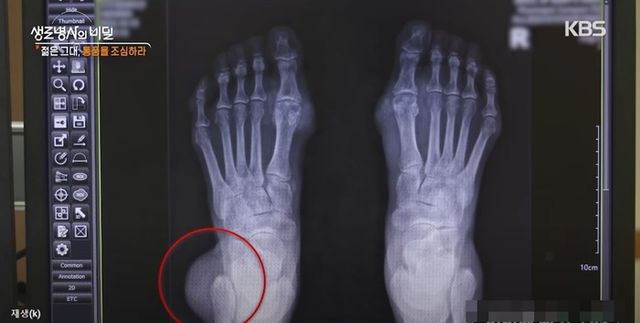

통풍 환자의 엑스레이 / KBS1 '생로병사의 비밀'

통풍이 생기면 관절에 염증이 생겨 엄청난 통증이 따른다. 통풍이 심하면 급기야 관절이 변형되기까지 한다.

통풍에 걸리면 무증상 고요산혈증, 급성 통풍성 관절염, 간헐기 통풍, 만성 결절성 통풍이 나타난다.